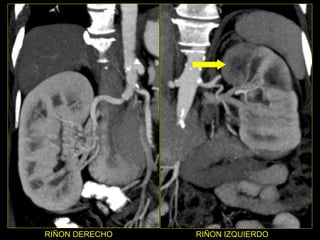

Caso # 3 ♀ , 5ta década de la vida.  Su síntoma principal fue dolor abdominal y por ello se le realizó un estudio de Urografía Excretora.  En él se sospecha de malformación arteriovenosa por lo que se envía a AngioTC. Se muestra estudio en fase simple, arterial, venosa y excretora, con cortes axiales y RMP coronales .

RIÑON DERECHO RIÑON IZQUIERDO

Hallazgos Caso # 3: Estudio negativo para la sospecha clínica que motivó su realización. Y en el que se demuestra, en la fase simple sin anormalidades, y posterior  a la ministración del medio de contraste hay un área hipodensa triangular en polo superior del riñón izquierdo, la cual se mantiene durante las fases arterial y venosa del estudio.